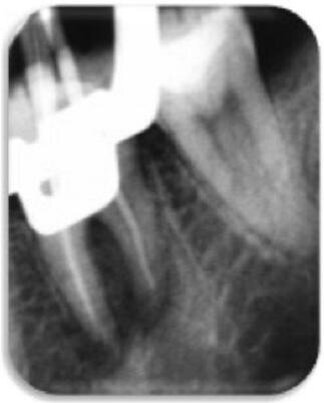

Pacjent zgłosił się ponownie dopiero po 6 miesiącach z objawami dyskomfortu podczas żucia, tkliwości opukowej, przejściowej opuchlizny oraz negatywnej reakcji na testy termiczne. Przeprowadzone badania radiograficzne potwierdziły wstępną diagnozę AP (Ryc. 2).

Do często podawanych następstw przeszczepu zębów zalicza się ankylozę i resorpcję korzeni.43,44 W opisywanym przypadku klinicznym resorpcję wierzchołkową korzenia dystalnego można powiązać z przerwaniem unaczynienia oraz przewlekłym stanem AP (Ryc. 5).3,8,45